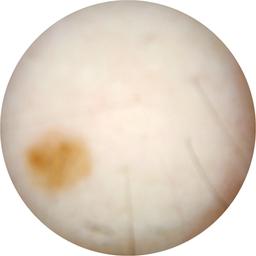

ISIC_9219276

Clinical

Field Value

acquisition_day 482

age_approx 55

anatom_site_1 Trunk

anatom_site_2 Posterior trunk

anatom_site_general posterior torso

concomitant_biopsy False

diagnosis_1 Benign

diagnosis_confirm_type single image expert consensus

family_hx_mm True

image_manipulation instrument only

image_type dermoscopic

lesion_id IL_5010026

patient_id IP_7167913

personal_hx_mm True

sex male